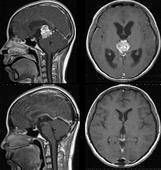

• 髓內(nèi)腫瘤

脊髓髓內(nèi)腫瘤在脊髓腫瘤中并不少見,髓內(nèi)腫瘤基本上分為兩大類:一類為原發(fā)性髓內(nèi)腫瘤;另一類為繼發(fā)性髓內(nèi)腫瘤。后者較少,常為顱內(nèi)腫瘤向椎管內(nèi)播散性腫瘤,如髓母細(xì)胞瘤...